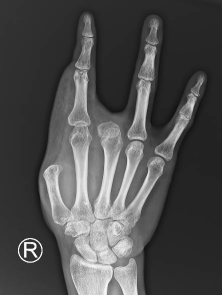

术前

皮瓣术后